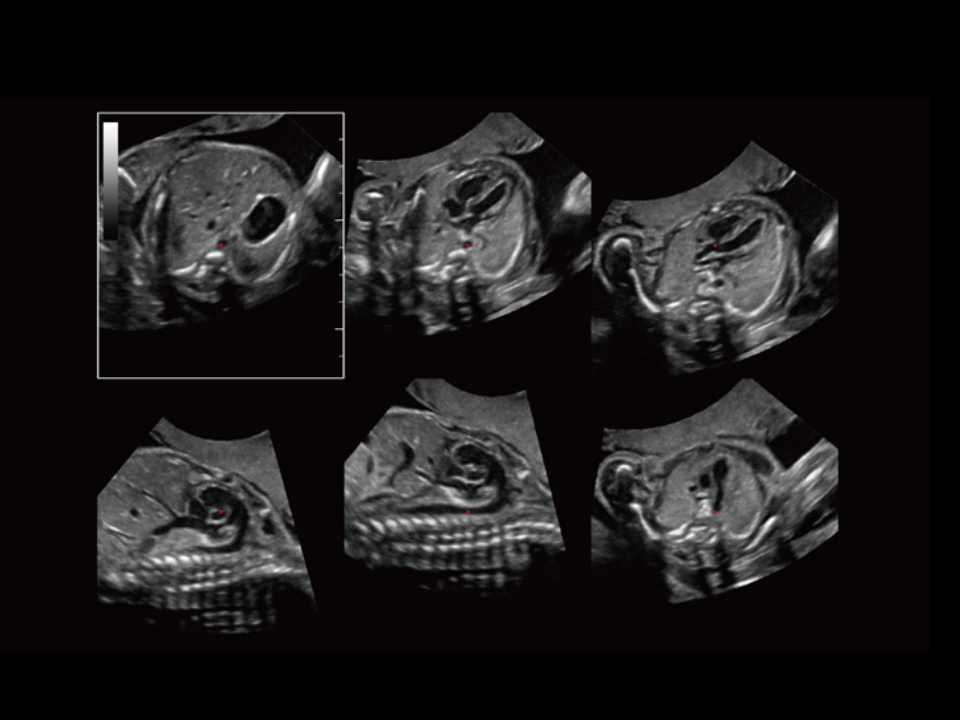

Thanks to the innovative, software-driven ZST+ platform, the Resona series is continuously evolving with the leading-edge technologies to meet the most challenging diagnostic demands in womenŌĆÖs health practice. More importantly, it is designed with the understanding that the wisdom of experts is always precious, and you need more intelligent partner for enhanced speed and confidence. Finally, Resona series with Zone Intelligence provides a total solution to help you with diagnostic confidence, efficiency, and standardization across different diagnostic challenges in todayŌĆÖs demanding and overburden hospital environment.